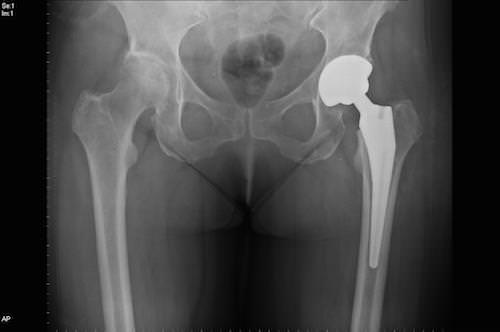

Если лечить заболевание с ранних стадий, можно предотвратить его прогрессирование. При обнаружении патологии на поздних стадиях назначается эндопротезирование сустава (замена искусственным аналогом).

Лечение 3 и 4-ой степени болезни оперативными способами проводится тогда, когда болезненность и обездвиживание в тазобедренном суставе имеют выраженную степень и не устраняется другими способами. Операция предполагает замену сустава искусственным протезом (эндопротезирование). Это устройство состоит из чашечки и головки. Изделие при установке человеку качественно заменяет физиологический сустав и позволяет вернуть подвижность. Другой альтернативы операции не существует.